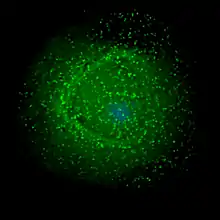

![]() | |

| Scanning electron micrograph of HIV-1 (in green) budding from cultured lymphocyte. Multiple round bumps on cell surface represent sites of assembly and budding of virions. | |